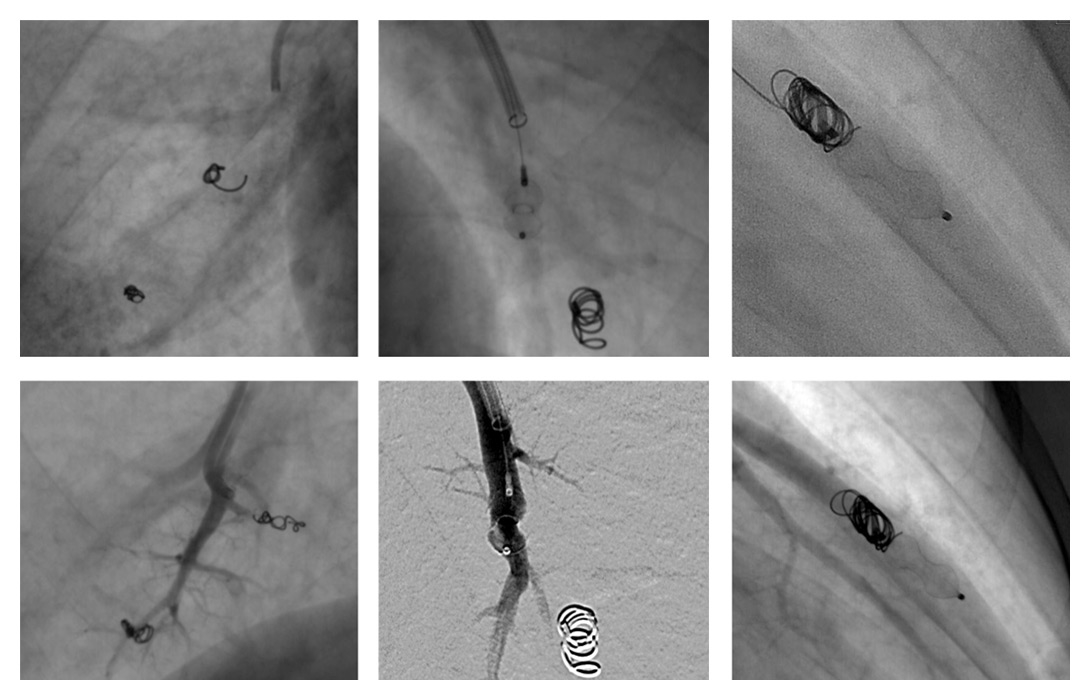

Figure 3

Examples of pulmonary arteriovenous malformation endovascular vaso-occlusions with vascular coils, plugs and combined treatment. Beneath each case is an angiographic control showing no vascular opacification beyond the occlusive device.

A total of 16 patients out of 72 followed-up for HHT (22%, 10 women, 6 men, m:f 1:1.67) presented a total of 54 PAVMs (1‒12, mean 3.9 PAVMs per patient,). Mean follow-up CT time was 41 months (1‒164). Based on the above-mentioned criteria for treatment, 11 patients were treated with vaso-occlusion for a total of 37 PAVMs throughout 18 procedures including 2 second treatments for 2 PAVMs (table 1). Eight patients were symptomatic and three presented asymptomatic PAVMs with feeding arteries larger than 3 mm (fig. 2). Mean procedures per patient was 1.64. Total treated PAVMs per total PAVM was 37/54 (68.5%). Nineteen PAVMs were treated with coils, 16 with plugs and 2 with combined treatment (table 2, fig. 3). Thirty-four (91.9%) PAVMs were successfully treated on the first intervention. Total recurrence rate per patient was 18.2% (2/11). Total recurrence rate per procedure was 12.5% (2/16). Total recurrence rate per treated PAVM was 5.4% (2/37). Two PAVMs (5.4%) treated by means of plugs needed a second procedure (at 10 days and 3 months), both treated by use of Amplatzer plugs. One case of a voluminous PAVM presented a large afferent artery of 12 mm diameter. A 15 mm long coil was initially used, but migrated into the main pulmonary artery and required a snare-assisted coil retrieval. Then a smaller sized 10/5 mm Tornado® coil was released, but it migrated distally into the left atrium, the left ventricle and finally the mitral valve. A snare-assisted coil retrieval was again successfully attempted (fig. 3). No clinical manifestation was observed. A second intervention a month later allowed for a coil-assisted successful vaso-occlusion, using multiple coils between 5 and 10 mm. Eighteen (94.7%) plug-treated PAVMs were successfully treated on the first intervention compared with 14 (87.5%) for coil vaso-occlusion, but Fisher’s test gave a p = 0.58 value, considered not significant. One new PAVM was observed during follow-up CT (0.29 per year) and was not treated because of its size. After the first intervention, mean procedure number per patient during follow-up was 0.63 (6 interventions for 11 patients). No major complication was observed. No surgery was needed in our series.